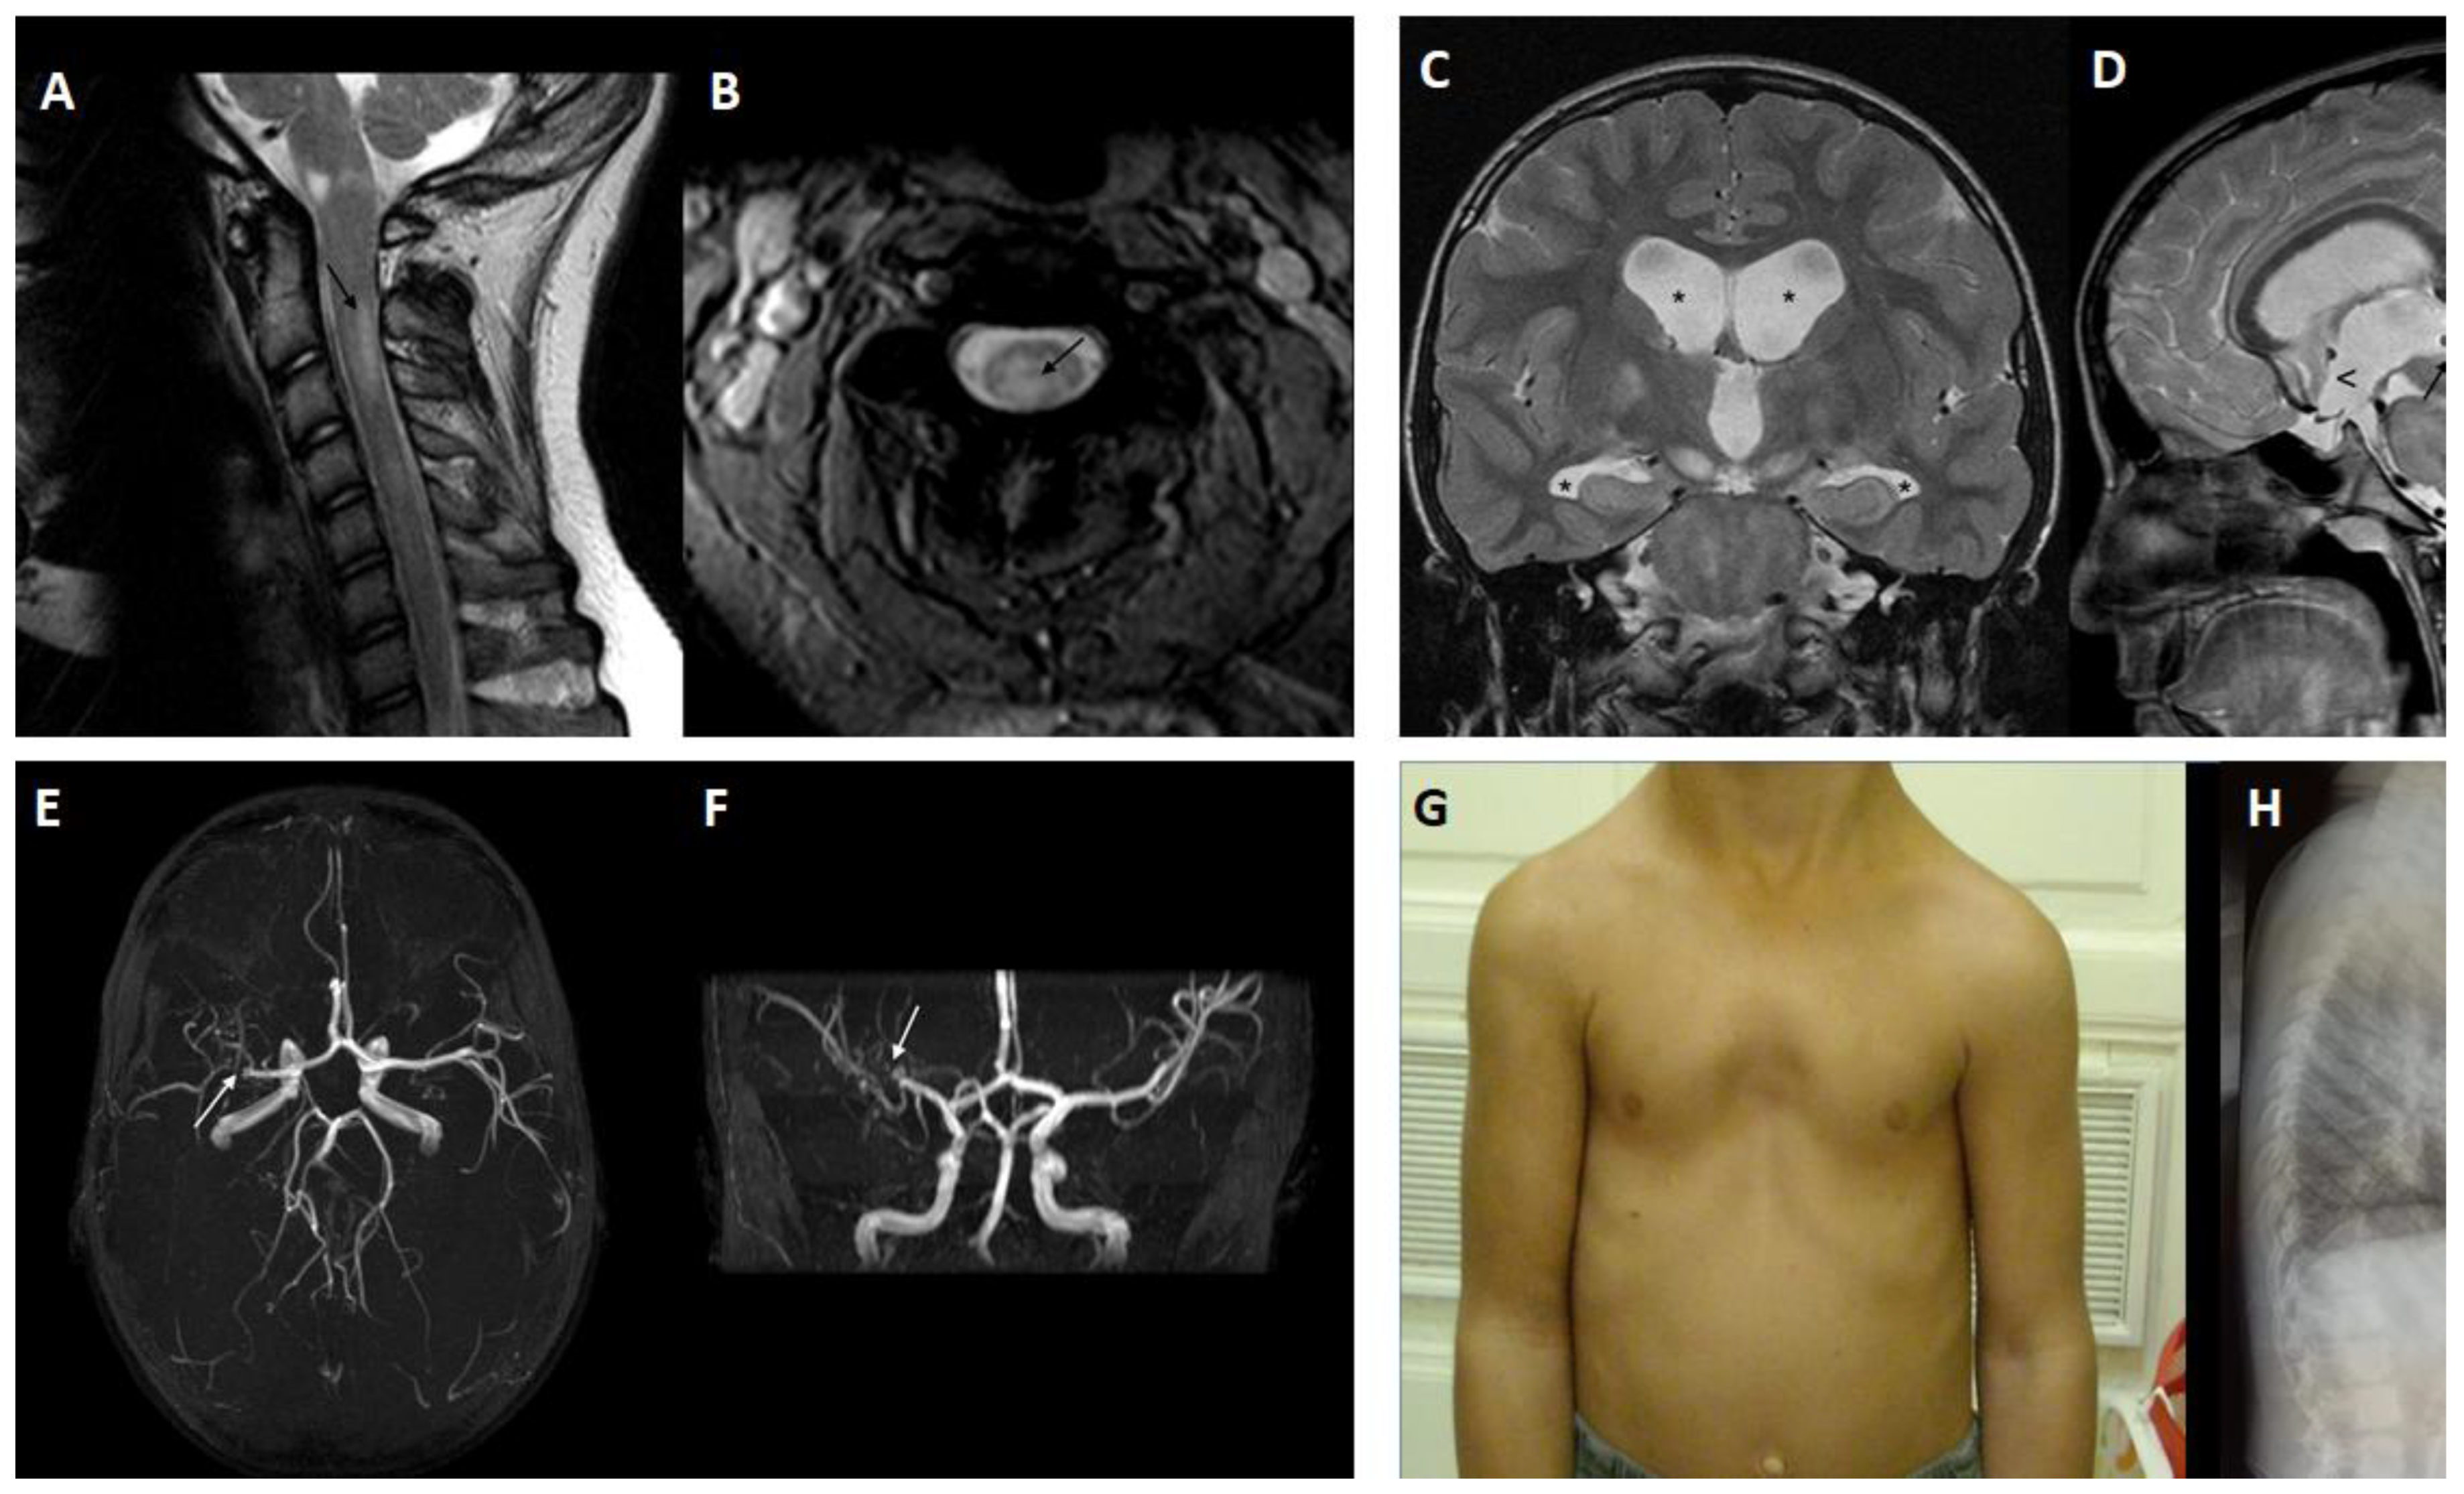

- D′Amico, A.; Ugga, L.; Cocozza, S.; Giorgio, S.; Cicala, D.; Santoro, C.; Melis, D.; Cinalli, G.; Brunetti, A.; Pappata, S. Multimodal evaluation of the cerebrovascular reserve in Neurofibromatosis type 1 patients with Moyamoya syndrome. Neurol. Sci. 2020, 42, 655–663. [Google Scholar] [CrossRef]

- Mirone, G.; Cicala, D.; Meucci, C.; d′Amico, A.; Santoro, C.; Muto, M.; Cinalli, G. Multiple Burr-Hole Surgery for the Treatment of Moyamoya Disease and Quasi-Moyamoya Disease in Children: Preliminary Surgical and Imaging Results. World Neurosurg. 2019, 127, e843–e855. [Google Scholar] [CrossRef] [PubMed]

- Santoro, C.; Di Rocco, F.; Kossorotoff, M.; Zerah, M.; Boddaert, N.; Calmon, R.; Vidaud, D.; Cirillo, M.; Cinalli, G.; Mirone, G.; et al. Moyamoya syndrome in children with neurofibromatosis type 1: Italian-French experience. Am. J. Med. Genet. A 2017, 173, 1521–1530. [Google Scholar] [CrossRef]